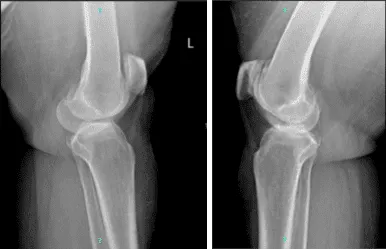

La paciente también trajo y presentó los resultados de radiografías de ambas rodillas. En el lado izquierdo, hay cambios degenerativos osteoartríticos leves. No hay fracturas agudas. Sin embargo, en el lado derecho, hay cambios degenerativos osteoartríticos moderados. Derrame articular. No hay fracturas.

Radiografía completa de la rótula de rodilla izquierda y derecha